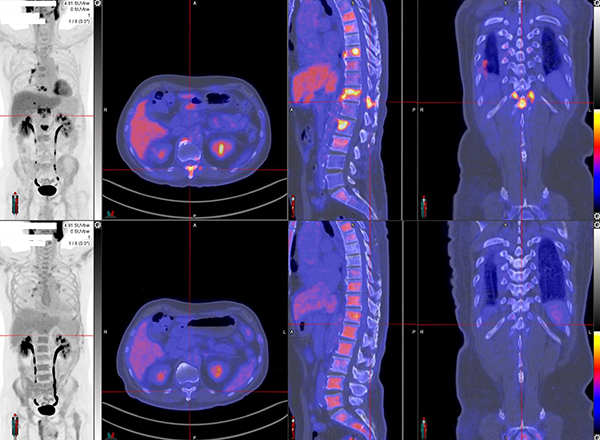

Dual tracer PET/CT (F-18 FDG and Ga-68 DOTATATE) are used for the metastatic evaluation of neuroendocrine tumor.